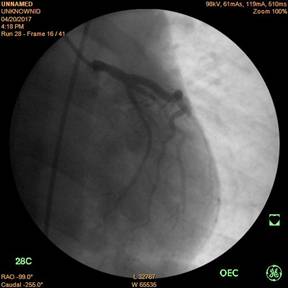

Động mạch vành trái trước và sau khi đặt stent

Bệnh nhân tên là Võ Hữu T., 30 tuổi, ở Phú Lộc, tiền sử hút thuốc lá và uống rượu nhiều. Bệnh khởi phát cách nhập viện 10 ngày với biểu hiện sốt, đau họng, ho, đau ngực sau xương ức tăng lên khi ho, đau ngực khi gắng sức. Các xét nghiệm cho thấy có hội chứng nhiễm trùng và tăng men tim, có dấu chứng tổn thương tim trên điện tâm đồ, làm siêu âm tim cấp cứu với kết quả giảm vận động buồng tim, chức năng tim giảm, được hội chẩn khẩn. Với quyết định chụp và can thiệp khẩn trương, bệnh nhân đã được nong và đặt stent động mạch vành trái.

Ngay sau đặt stent động mạch vành, bệnh nhân giảm đau ngực nhiều, men tim giảm, cảm giác khoẻ hơn.